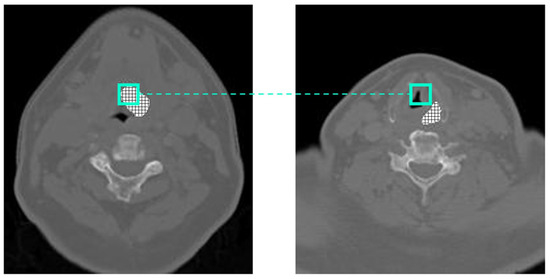

Figure 4.

Displacement between center and edge slice of GTV.

Figure 4 shows the displacement in the GTV when considering a window at the same position in the axial center of the GTV compared with an edge slice. In Figure 4, the center of the GTV has shifted 10 pixels to the right and 4 pixels down from the center to the edge. When calculating the displacement in the GTV from slice to slice across the z-axis, the GTV shifts on average 1.5 pixels on the x-axis and 1.53 pixels on the y-axis. While larger kernel sizes may be able to capture both centers across two or more slices, they will never be appropriately aligned, which could lead to erroneous results the farther we get from the center of the GTV. Pre-existing methods that take advantage of inter-slice connectivity, such as 3D CNNs or CRNNs, convolve or push information forward uniformly across the same pixel locations, even if those pixels are inadequately aligned.